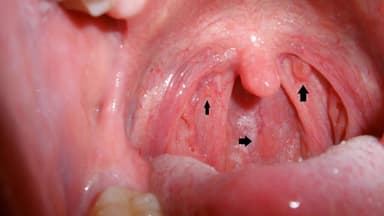

– Sốt cao, họng nuốt vướng: Nếu thấy mình bị sốt cao, đau rát họng, nuốt vướng, kèm theo cảm giác uể oải, nhức đầu thì bạn đã bị viêm amidan. Theo đó, hô hấp cũng trở nên khó khăn, nhất là vào buổi đêm, khiến xuất hiện tình trạng ngáy to.